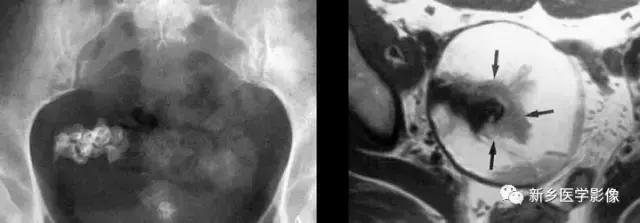

子宫平滑肌瘤(纤维瘤)

主要位于盆腔内,表现为不均一的点状钙化